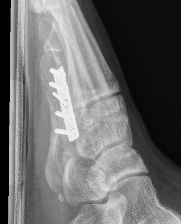

Displaced fracture Nonunion

Screw fixation Zone 2 nonunion

Screw fixation Zone 3 nonunion